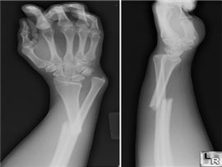

盖氏骨折

盖氏骨折是桡骨中下三分之一之一骨折和下尺桡关节脱位。早在1929年,法人就称之为...

尺骨骨折、桡骨头脱位、桡骨骨折